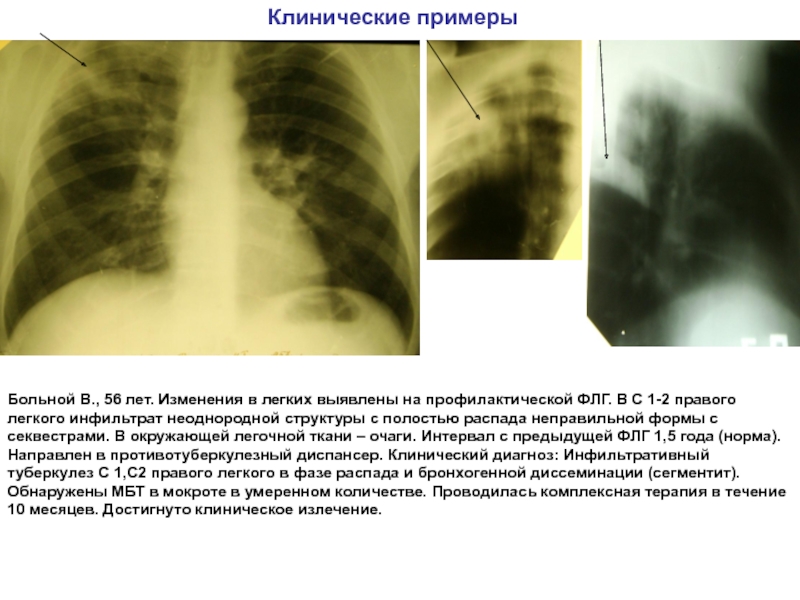

Иллюстрации по теме очагового и инфильтративного туберкулеза

Раздел: Фотодневник открытий